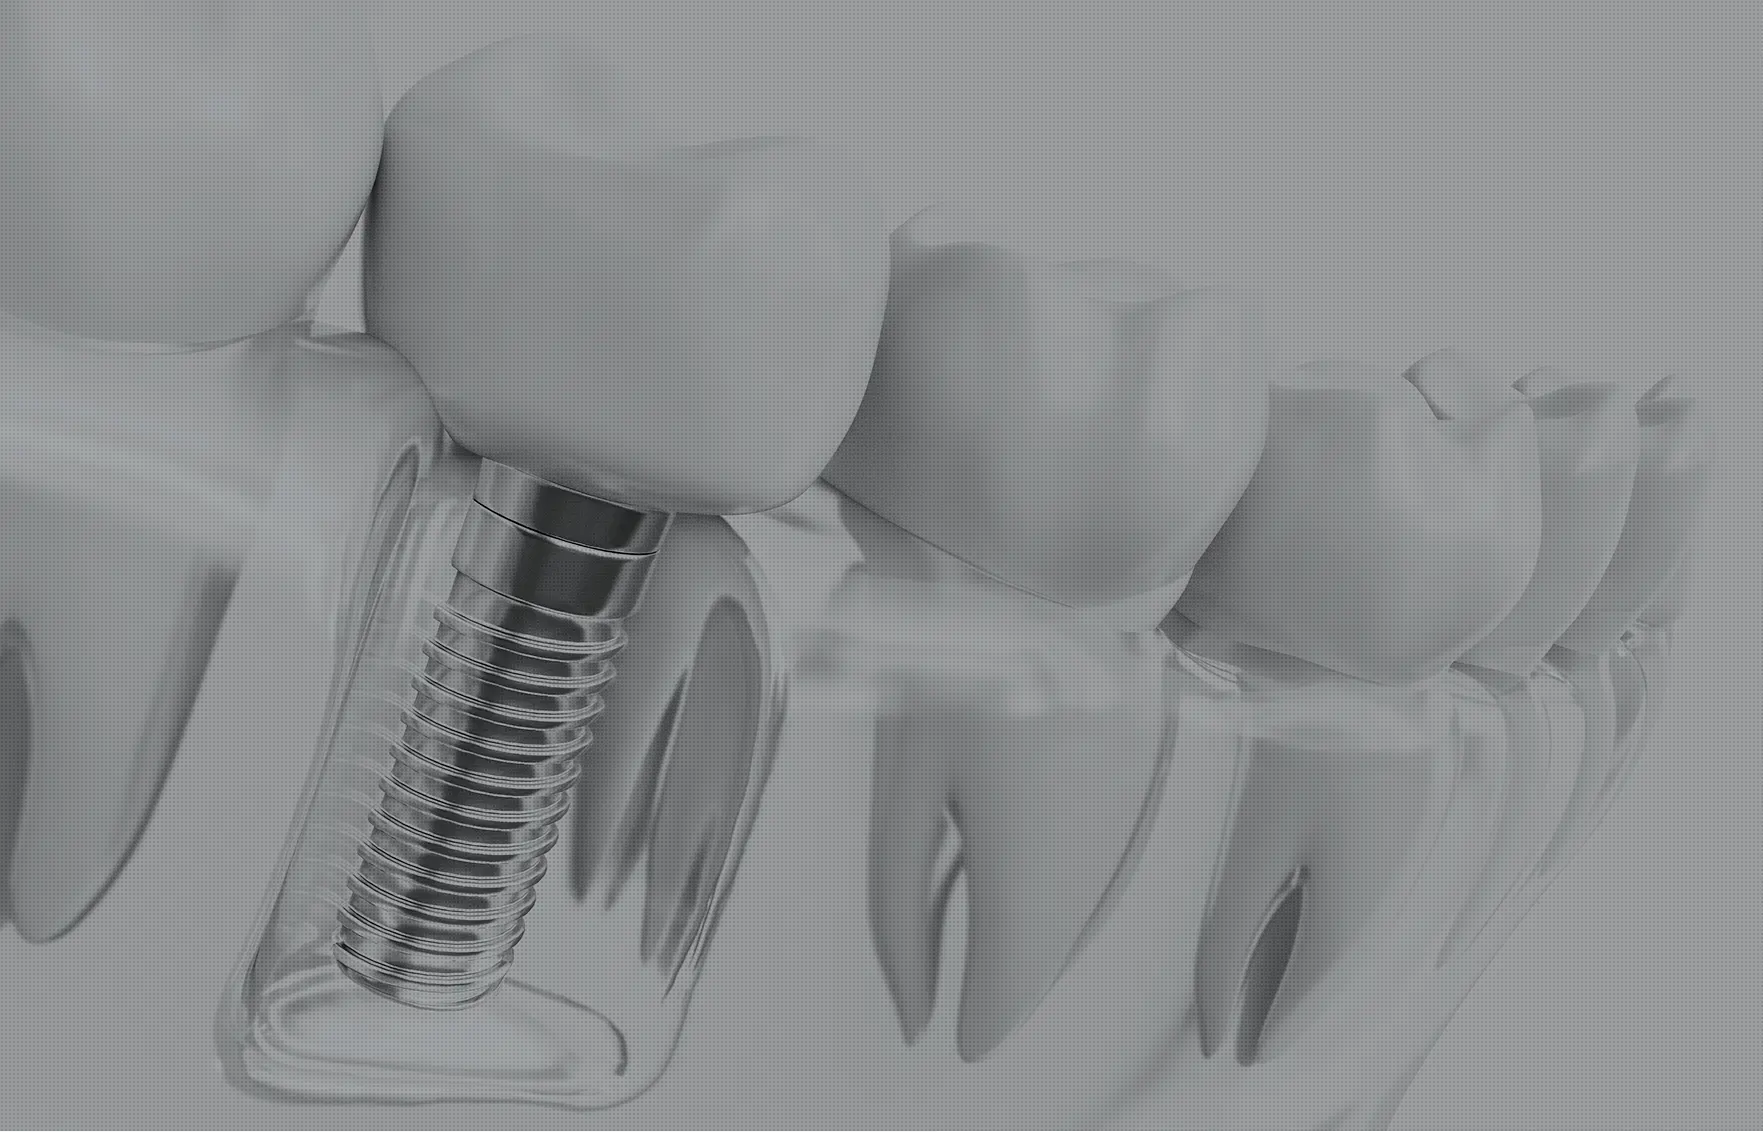

インプラントは、顎の骨に固定する治療のため、天然の歯のような噛み心地をめざせる上、噛む力が顎の骨に伝わりやすい特徴があります。その刺激によって、顎の骨がやせていく変化を抑えることも期待できます。

顎の骨に人工の歯根を埋め込み、その上に白い歯を被せる構造のため、安定しやすい治療法です。ぐらつきが少なく、噛むときの違和感を抑えられるインプラントで、食事の楽しみを取り戻しましょう。

シミュレーションをもとに、適切な位置へ人工歯根「インプラント体」を埋め込みます。

当院ではサージカルガイドを活用し、必要以上の切開を避け、歯ぐきに小さな穴を開けるだけで的確な手術を行うことが可能です。これにより術後の痛みや腫れを軽減できます。患者さまの負担を少なくした、安全性の高い治療を実践しています。

インプラント体が骨と結合するまでには、通常2〜3ヶ月ほど必要です。安定が確認できた段階で、白い人工歯を製作するための型取りに進みます。